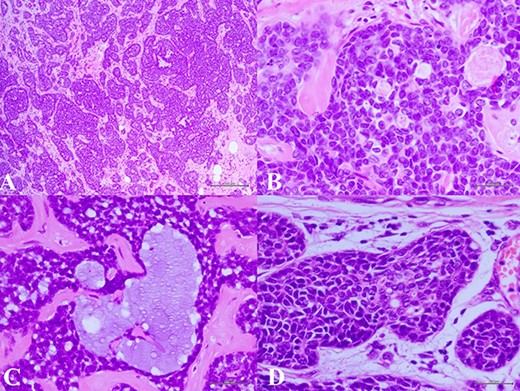

(A) Histologic examination showed the neoplastic cells predominantly arranged in a solid growth pattern (100×). (B) The true glandular spaces lined by luminal-type epithelial cells (600×). (C) The pseudolumens containing watery basophilic mucopolysaccharides basement membrane-like materials rimmed myoepithelial cells (400×). (D) Intraductal components composed of a dual population as the invasive areas (600×)